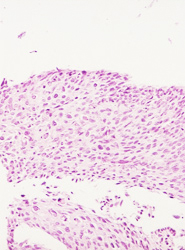

El resultado de una valoración colposcópica de paciente con lesión displásica siempre será confirmado por el estudio histopatológico que realiza el médico anatomopatólogo (estudio de la biopsia tomada en la colposcopía) . A continuación presentamos imágenes histológicas con sus diagnósticos.

• Lesion de alto grado, con anisocitosis y anisocariosis severas, perdida de la cohesividad y orientacion celular.